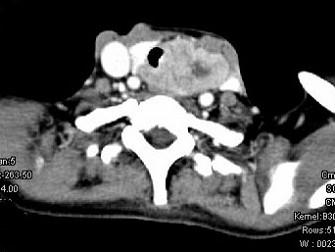

问题 女,50岁,左下颈部扪及一质硬、表面高低不平的包块,肿块逐渐增大,现感吞咽困难,CT如图所示,最可能诊断为 ( )

选项 A、甲状腺原发淋巴瘤 B、颈部神经鞘瘤 C、食管癌 D、喉癌 E、甲状腺癌

答案 E